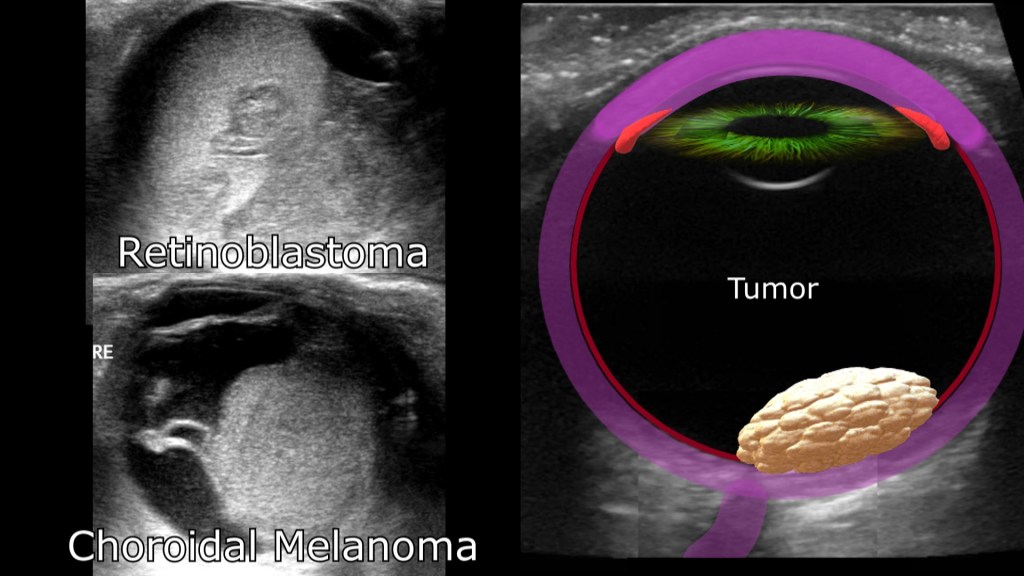

Intraocular Tumors

Ocular tumors range from benign to malignant, ultrasound can be used to identify the presence of, size and sonographic appearance (i.e. cystic, solid heterogenous) of the lesion.

Malignant

Ocular Melanoma

- most common ocular cancer

- starts in the pigment cells of the eye

- usually starts in the uvea/choroid

Retinoblastoma

- rare eye cancer seen in children

- develops from the immature nerve cells of the retina

- sometimes discovered incidentally on personal photos

- child may lose vision/need surgical removal of the affected eye

Benign intraocular tumors are non cancerous lesions like choroidal hemangioma, eye moles and cavernous hemangiomas and can be seen within or behind the eye.